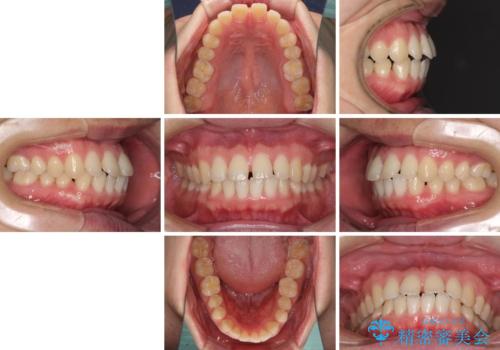

- 上の前歯の隙間を気にして来院された患者様です。

インビザラインにより、上下の歯列を側方に拡大しつつ、前歯の隙間を閉じていくこととしました。

1日22時間の装着時間をしっかりと守ってくださったので、隙間がきれいに閉じ、口元の突出感も改善することができました。